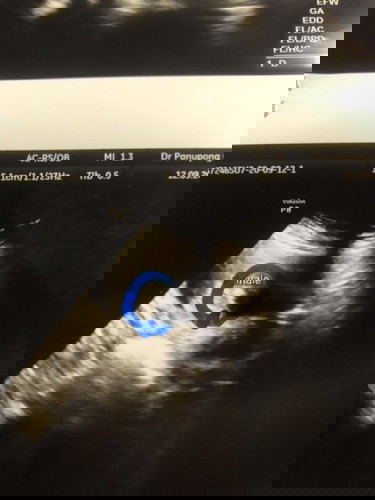

สอบถามแม่ๆว่าลูกสาวชัวร์มั้ยคะ

หมอบอกไม่ชัดเจนแค่บอกจะพิมพ์ลูกสาวไว้ก่อน อยากทราบว่าแม่ๆคนไหนได้ลูกสาวแล้วเหมือนใบซาวเราบ้างคะ ปล. อยากได้ลูกสาวมากจ้า😅

ช่วยดูให้หน่อยค่ะว่าผู้หญิงหรือผู้ชายค่ะ คุณบอกว่าน่าจะผู้หญิงค่ะ

แม่บ้านนี้ก็ลูกสาวค่ะ ข้างบนช้ายมือ F

ผู้หญิงนะค่ะ😍😍ไม่มีแหลมๆ